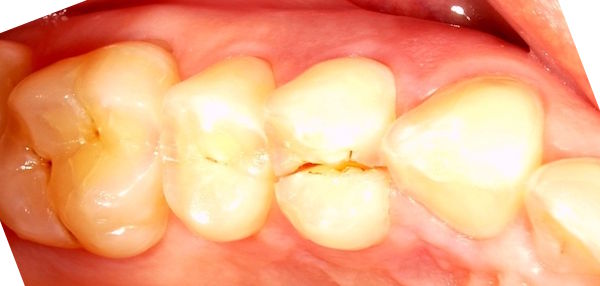

Ein schiefer Interkuspidalkontakt zwischen den oberen und unteren Seitenzähnen kann ein Diastema verursachen, in das beim Essen Speisereste hineingestopft werden.

Bei schiefen Ebenen kann ein kleiner Interkuspidalwinkel eine grosse Spaltkraft verursachen. Dies zum Beispiel bei einer abgenützten Füllung oder tiefen Verzahnung.

Beachte: Die Fraktur verläuft mesial 2 mm weit durch eine initiale Karies, zentral 6 mm neben einer Amalgamfüllung, und distal 3 mm lang mitten durch eine intakte Kompositfüllung. Diese ist mittig gespalten, aber nirgends vom Zahn abgerissen. Das Zentrum der Amalgamfüllung ist nicht gespalten.

Der Patient ist ein Heavy biter und kam seit Jahren immer wieder mal um Hyperbalancen einzuschleifen. Zudem war dieser +6 der letzte Molar links oben.

Auch auf diesem Röntgenbild ist weder die Hyperbalance noch der kleine Höckerwinkel mit der vertieften Zentrik sichtbar. Die initiale Karies war klinisch nicht sichtbar.